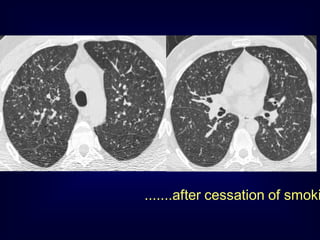

A professional diver..........

.......after cessation of smoki